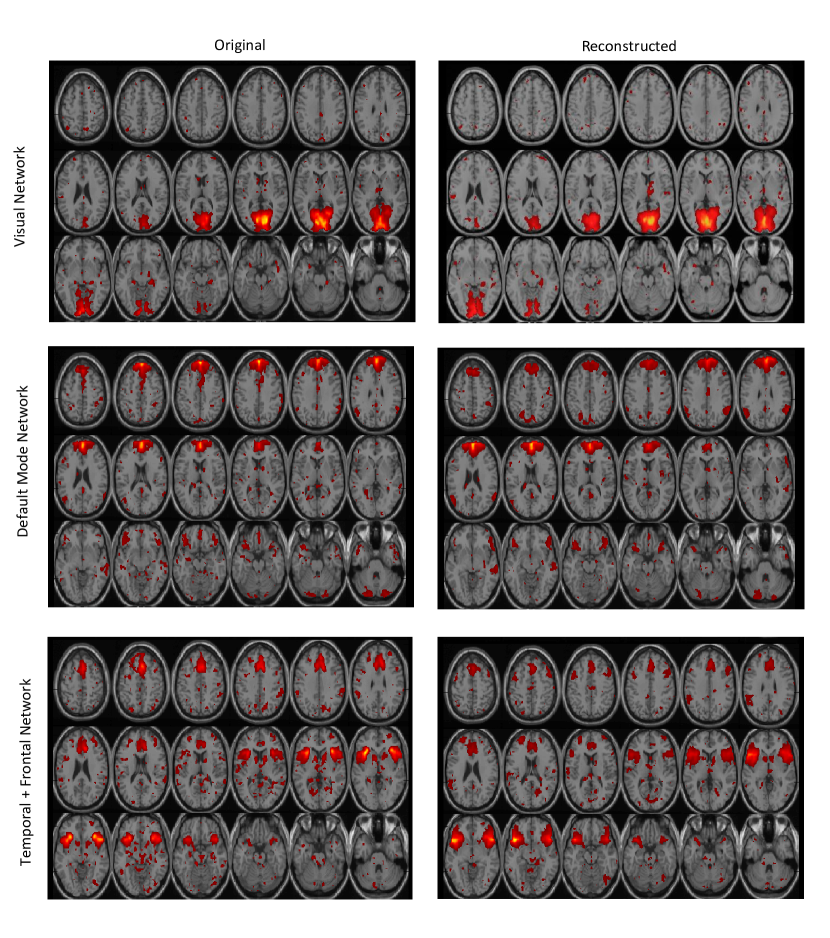

On the fMRI data reconstructed using the proposed DTSR method, we identified 56 ICs from the mean maps of reconstructed fMRI data of all 20 subjects. We manually arranged these ICs into various RSNs stated above. The spatial maps of some RSNs discovered by the fully available data and the DTSR reconstructed data are shown in Fig.6 to Fig.7. Left part of each figure represents networks identified using the fully available data and the right part represents networks identified using the DTSR reconstructed data. It is clear that spatial activation maps of RSNs obtained from the reconstructed data overlap significantly with the RSNs of the fully available fMRI data. From now onwards, ICs of DTSR reconstructed data will be mentioned as simply DTSR ICs (DTSR-ICs) and ICs of fully sampled original data will be mentioned as raw ICs (RICs). It is noticed that DTSR-IC maps are more enhanced compared to the RIC maps. This is perhaps due to denoising inherent within the CS reconstruction framework.

Refer to caption

Figure 7: Axial view of spatial maps of various RSNs where the left part of each figure represents networks identified using the fully available (original) data and the right part represents networks identified using the DTSR reconstructed data. Number in brackets below each image represents independent component (IC) number obtained after group ICA.

Two observations are in order from the qualitative results (Fig.5-6): (i) intrinsic resting state networks are consistent and comparable to the fully sampled fMRI data. Hence, crude estimate of regularization parameters is sufficient for reconstruction; and (ii) the fidelity of the proposed method in maintaining temporal information is established via consistency of results and via observation of all RSNs.